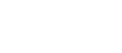

Contrast enhancement within the thrombus is a pathognomonic sign for tumour thrombosis, while no enhancement indicates benignity. CEUS has been reported to have high sensitivity and specificity (90.9% and 100%, respectively) in diagnosing malignant thrombus[30,31] [Figure 6].

Figure 6. Thrombosis of portal vein (main, right and left branch) in a 62-year-old man recently diagnosed with NASH-related cirrhosis. At CEUS examination, with SonoVue, the thrombus presented arterial hyperenhancement (A) with washout in the late phase (B).